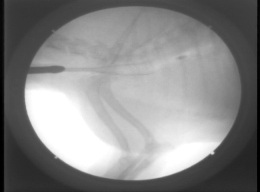

図3 同症例の透視下でのステント展開時の様子。